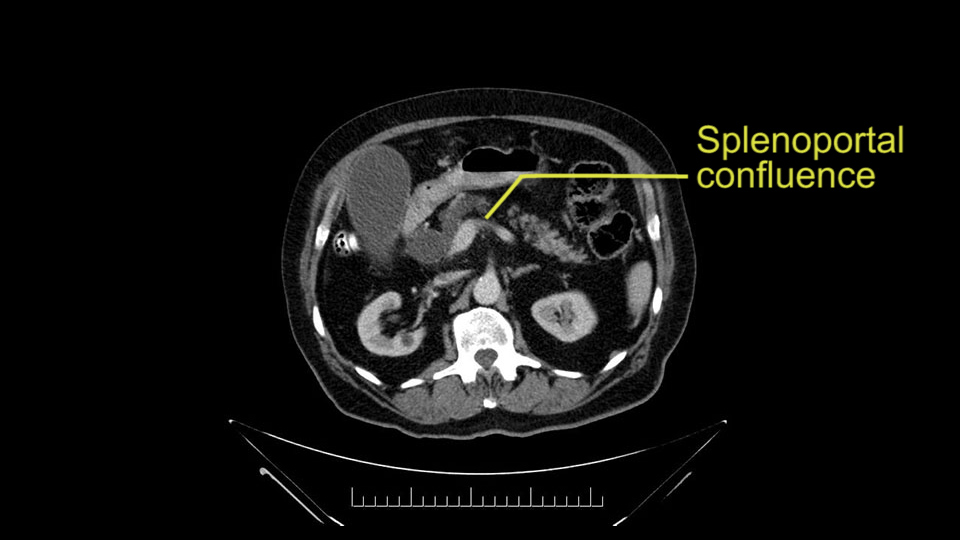

The next item that I would look at: the issue would be the vessels and usually start at the portal vein, watch the portal vein, follow it down, down-down-down to the neck of the pancreas - which is here - and there’s no impingement by tumor, which is great. The SMV and the splenic vein, which is here. The splenic vein junction is normal, which is great.

The next thing we always evaluate, although we do not expect invasion to the portal veins in this case, we must always trace the path of the portal vein, in both directions, from top to bottom. The splenoportal confluence and the superior mesenteric vein, which in this case does not appear to be compromised.

Por otro lado, siempre evaluamos -aunque en este caso no esperamos que haya invasión de los vasos portales-, siempre hay que hacer el recorrido de la vena porta, en ambos sentidos, de arriba hacia abajo; el confluente esplenoportal y la vena mesentérica superior, que en este caso no aparentan estar comprometidos.